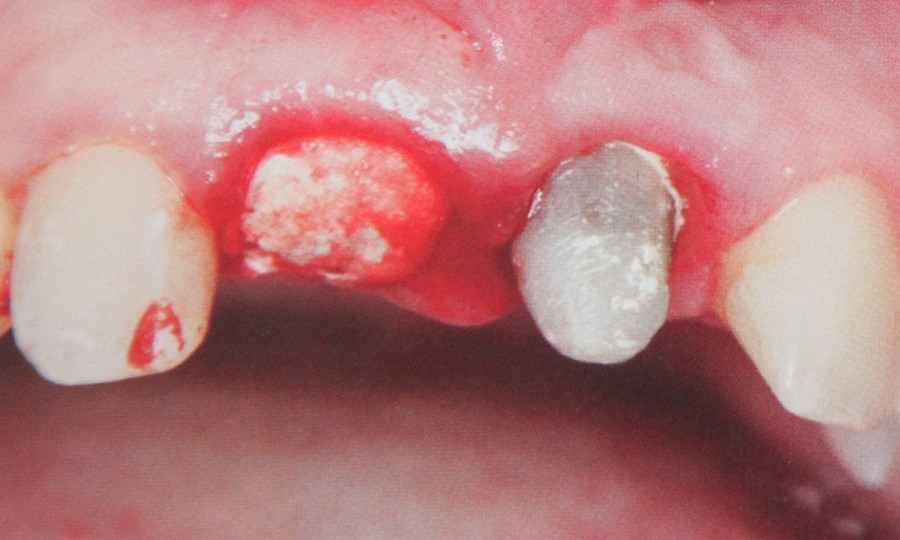

Presupune refacerea structurii dintelui utilizand lucrari protetice atunci cand caria dentara a afectat dintele intr-o masura prea mare pentru a putea fi remediat prin intermediul unei plombe. Daca dintele nu mai poate fi salvat si este extras spatiul lipsa poate fi completat fie printr-o lucrare protetica fie cu ajutorul unui implant. Daca pacientul pierde un numar mai mare de dinti se confectioneaza o proteza dentara.

Implantele dentare reprezinta la ora actuala singura posibilitate de a inlocui dintii lipsa prin protezare fixa rezultand o dentitie foarte apropiata de dintii naturali. Implantele dentare sunt niste radacini artificiale realizate din titan care se insera in os. Dupa o perioada de aproximativ 6 luni perioada necesara pentru integrarea implantului, acestuia i se ataseaza un bont protetic pe care ulterior se fixeaza coronita de ceramica sau proteza.